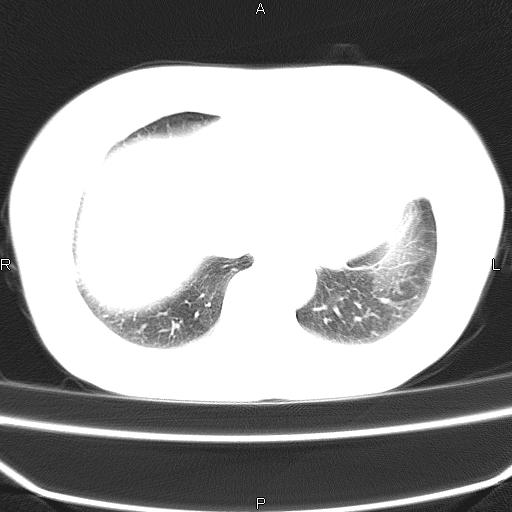

患者,女,66岁。健康体检胸部透视发现右上肺片状阴影。既往无不适,患者自诉三个月前曾有低热病史体温37.5左右一周。用药后缓解。至今无其它不适。请老师们指导指导。

考虑:右肺上叶周围型肺癌(分叶状肿块+砂粒状钙化+胸膜尾征)。

病灶见明显分叶、大小较大(大于3cm?),老年人,多考虑:肺癌,建议穿刺活检。

典型的中心型肺癌,尖段支气管阻塞。

以下是引用dyqct在2010-6-3 9:32:00的发言:[br]考虑:右肺上叶周围型肺癌(分叶状肿块+砂粒状钙化+胸膜尾征)。

不像中央型啊

右肺上叶周围型肺癌可能性大。

考虑:右肺上叶周围型肺癌